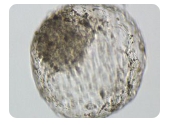

黄冈 第三代试管婴儿费用详细介绍第三代试管实际上是植入前胚胎基因诊断技术。这项技术是在第一代和第二代试

管的基础上发展起来的,用于治疗不孕症。目前,黄冈没有医院可以做第三代试管技术的考虑。当然,根据其现有数